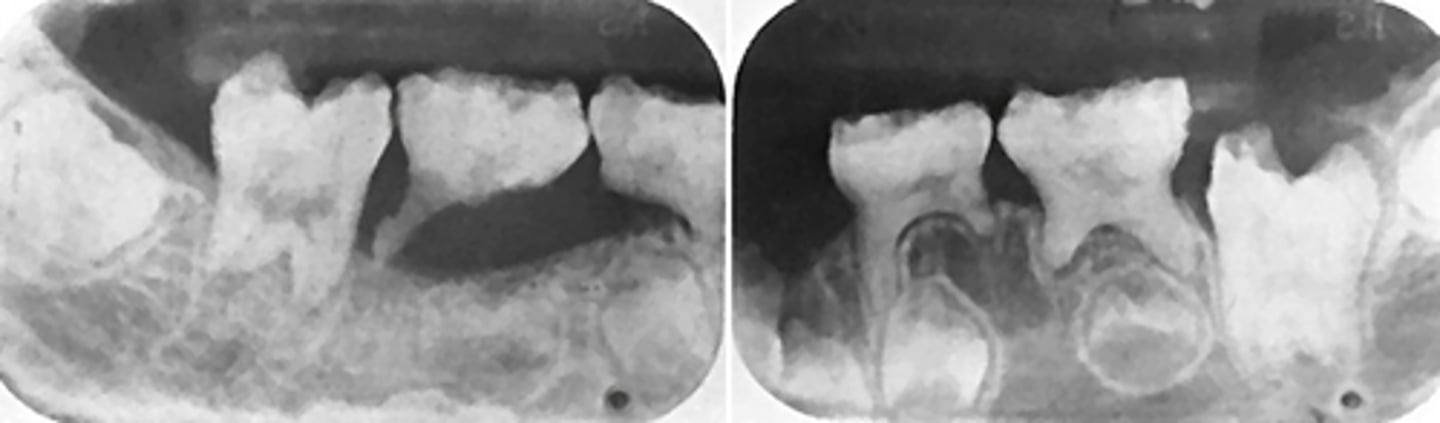

Patient has DJD.

The top images show the subchondral/ Ely cyst, a pseudocyst of connective tissue, granular tissue and osteoid, the bottom images show the same patients left side with broad erosion, a lack of cortication, loss of joint space.

What is the diagnosis of the patient based off these radiographs and what are the features? (Top images = patients right condyle) (bottom images= same patients left condyle)